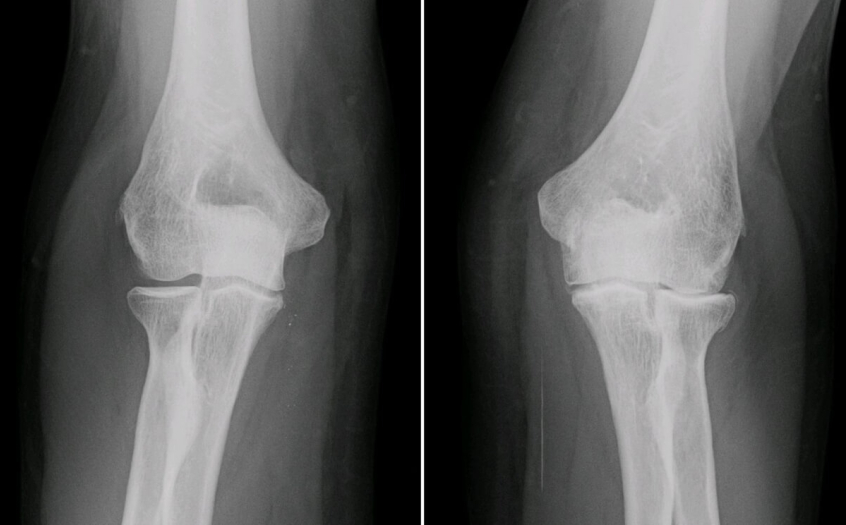

Osteoarthritis is the most common type of arthritis, according to the National Institute of Arthritis and Musculoskeletal and Skin Diseases (NIAMS), that affects the cartilage, the slippery tissue protecting the ends of bones that meet in a joint.

The condition usually develops with age and mostly affects hips, knees, and fingers. According to NIAMS, roughly 27 million Americans over the age of 25 suffer from osteoarthritis.